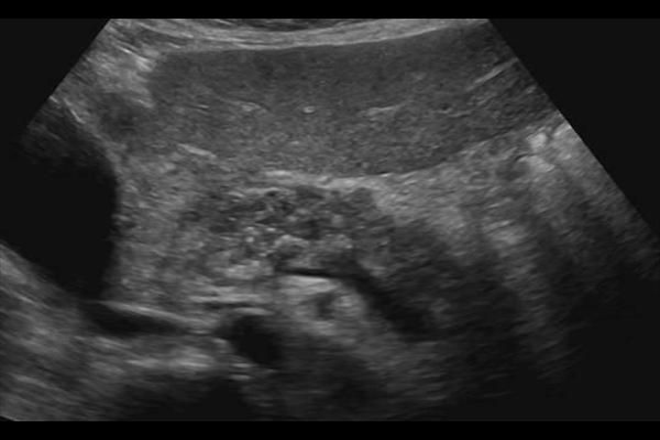

Se encontraron hallazgos ecográficos los cuales muestran la presencia de la lesión ocupante de espacio como la dilatación del colédoco, la presencia de adenopatías retroperitoneales, metástasis hepáticas en menor proporción, el tamaño las lesiones oscilo entre 8mm y 120mm, con media de 37.5 mas menos 16mm, con una localización mas frecuente en la cabeza del páncreas, la imagen ecografía mostró imágenes hipoecogenicas en un 77%, 15% heterogéneas, isoecogenicas y hiperecogenicas en un 3%, de consistencia solidad en un 79%, liquida 10%.